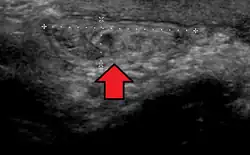

In the diagnosis of abdominal hernias, imaging is the principal means of detecting internal diaphragmatic and other nonpalpable or unsuspected hernias. Multidetector CT (MDCT) can show with precision the anatomic site of the hernia sac, the contents of the sac, and any complications. MDCT also offers clear detail of the abdominal wall allowing wall hernias to be identified accurately.[19]